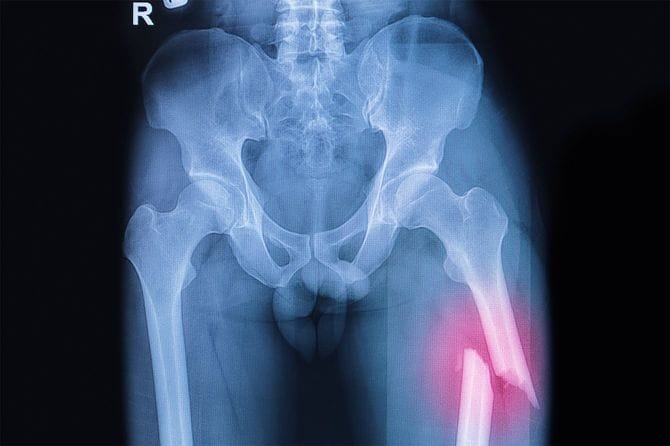

関西在住の大学生、湖西信治郎さん(仮名・現在大学4年)の両親は、幼い頃に離婚。10代の頃に高齢の祖母と同居し、やがて認知症を発症した祖母を、母親とともに在宅介護してきた。母親はフルタイムで働く保育士だ。男子大学生は、母親が帰宅するまでに、デイサービスから帰ってくる祖母を迎え、夕食の支度をし、祖母に食べさせる。しかし認知症のせいなのか、もともとの性格なのか、祖母は娘や孫の言うことを素直に聞かないばかりか、時には暴言を吐いて暴れることも。男子大学生は、介護の悩みや愚痴を相談する相手もなく、ひたすら耐えていたが、あるとき、祖母が大腿骨を骨折して歩行困難になる――。

2018年11月。心配していたことが現実となった。89歳となった祖母がいつものようにうとうとしていたところ、バランスを崩して椅子から落ち、床に転がったまま痛みを訴え、起き上がれなくなったのだ。母親と湖西さんは救急車を呼び、病院へ。

祖母は大腿骨を骨折しており、入院することに。

2019年3月。祖母はリハビリ病院を経て、退院した。骨折前は杖をつけば自立歩行ができていたが、退院した祖母は、誰かの介助なしでは歩行できなくなっていた。医師から、「杖を使っての歩行は、転倒のリスクが高いため危険です。歩行器を使ってください」と指導を受ける。